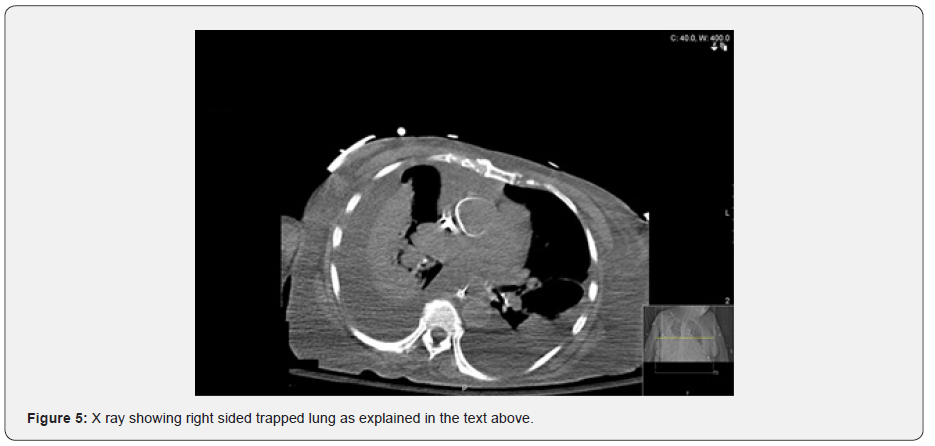

X ray on the following was now significant for a right hydro-pneumothorax in the same location. Effusion the left still unchanged from that on the left (Figure 4). The patient continued to be at her baseline health status and had no active complains from the effusions. As the patient remained stable, she was discharged to the nursing home with regular outpatient hemodialysis sessions and aggressive treatment of her hypertensive heart disease with carvedilol, amlodipine, hydralazine and lisinopril (Figure 5).

Chest radiography post initial thoracentesis would show thickened visceral pleural cortex. CT scan would also be helpful in visualizing the thickened pleura and trapped lung tissue, but it may be falsely thickened due to overlying exudate and debris [6]. Analysis of the pleural fluid should be done to rule out malignant effusion, so treatment can be directed towards symptomatic relief as it has a short-expected survival [7]. Definitive treatment is surgical decortication but is reserved for patients with symptoms and who are able to tolerate. Bronchial obstruction is ruled out before surgical intervention is planned [6].

In this case, pleural effusion was the cause for formation of trapped lung. Imaging post thoracentesis did not show resolution of the effusion. Following imaging showed formation of hydro-pneumothorax in the same location. Patient was not a surgical candidate due to age. She was only managed medically for her diastolic heart failure and through ultrafiltration to prevent re accumulation of fluid.